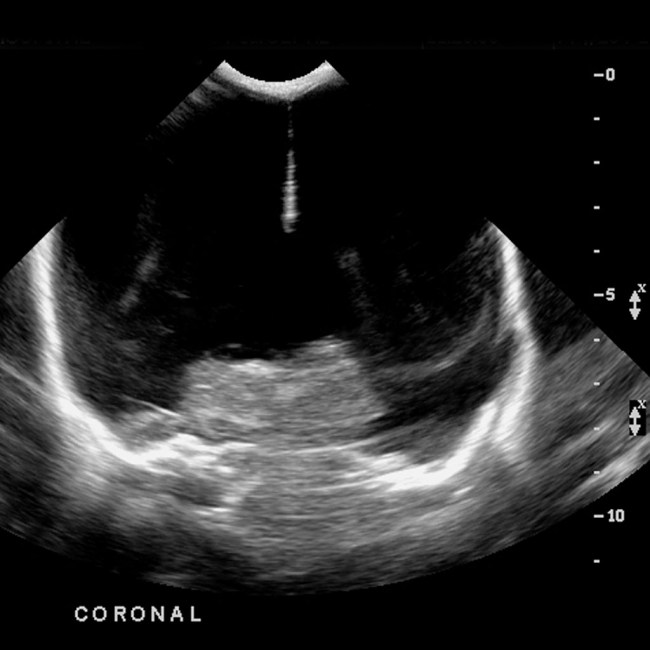

ΔΑΝΕΙΖΟΜΑΙ ΑΥΤΗ ΤΗΝ ΕΙΚΟΝΑ ( http://radiopaedia.org/images/151709) ΑΠΟ ΙΣΤΟΤΟΠΟ ΑΝΘΡΩΠΙΝΟΥ ΑΠΕΙΚΟΝΙΣΜΟΥ ΓΙΑ ΝΑ ΔΕΙΞΩ ΠΩΣ Η ΕΙΚΟΝΑ ΤΗΣ ΥΔΡΑΝΕΓΚΕΦΑΛΙΑΣ ΜΟΙΑΖΕΙ ΣΤΟΝ ΥΠΕΡΗΧΟ ΣΕ ΑΥΤΟ ΤΟ ΠΕΡΙΣΤΑΤΙΚΟ.

ΣΤΟΝ ΙΣΤΟΤΟΠΟ ΑΥΤΟ ΠΕΡΙΓΡΑΦΕΤΑΙ Η ΕΙΚΟΝΑ ΤΗΣ ΥΔΡΑΝΕΓΚΕΦΑΛΙΑΣ. Ο ΕΓΚΕΦΑΛΙΚΟΣ ΙΣΤΟΣ ΑΝΤΙΚΑΘΙΣΤΑΤΑΙ ΑΠΟ ΕΓΚΕΦΑΛΙΚΟ ΥΓΡΟ.